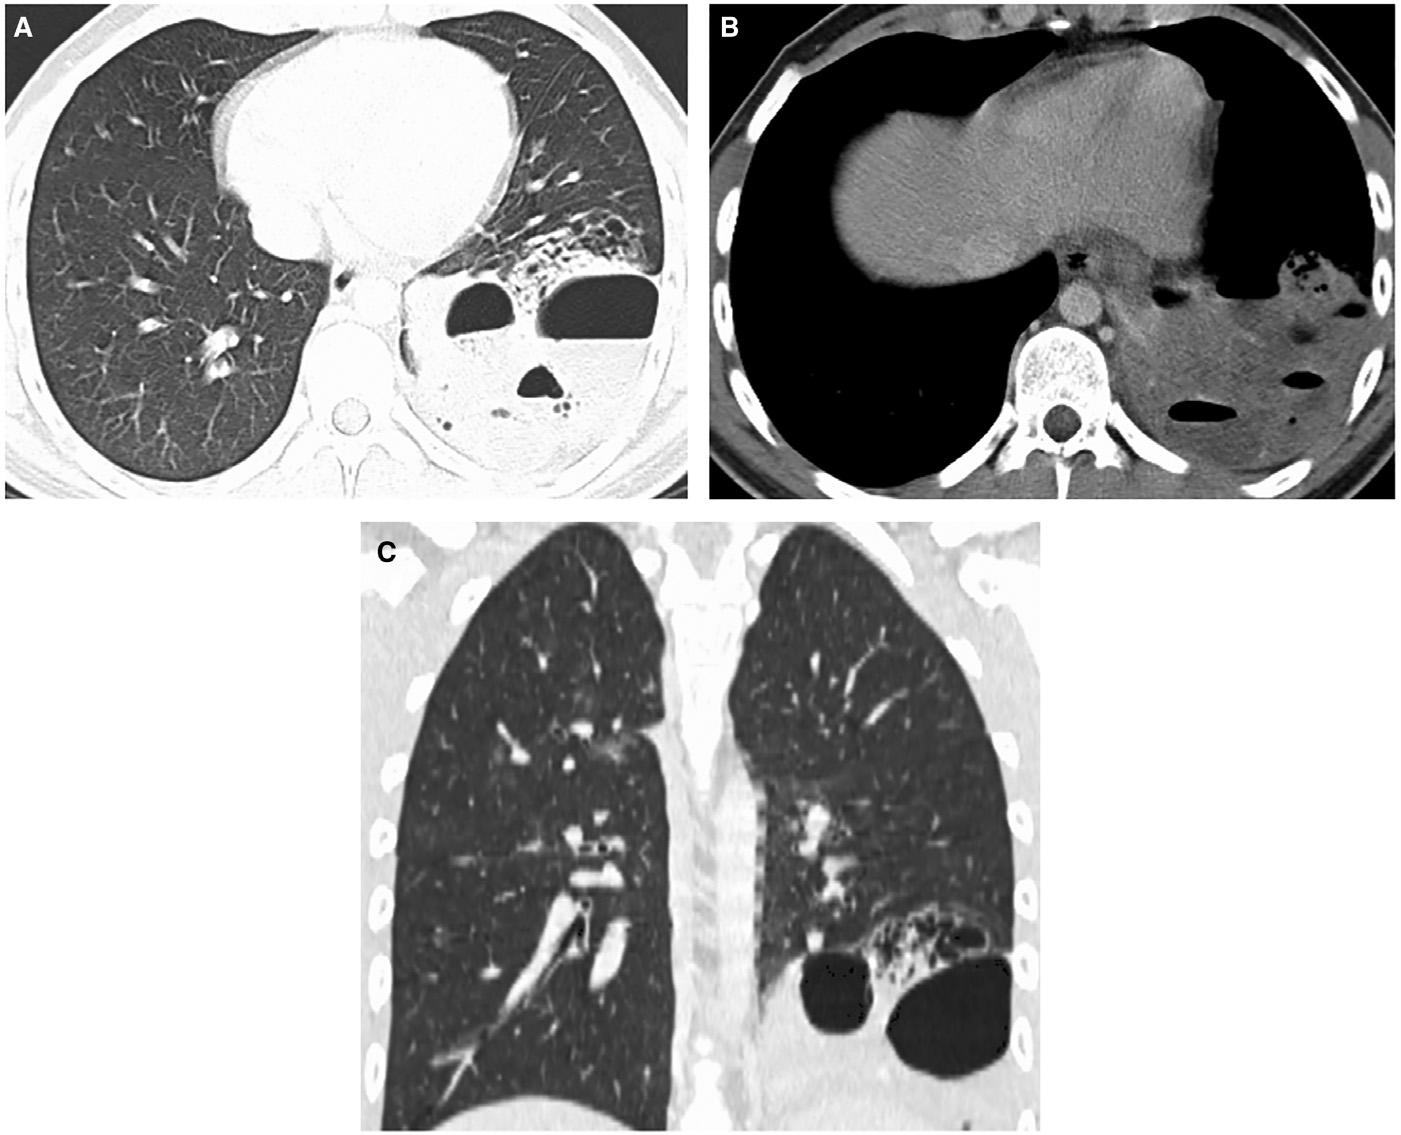

實驗室檢查顯示白細(xì)胞計數(shù)13.6×109/L↑(中性粒細(xì)胞79%;淋巴細(xì)胞12%),C反應(yīng)蛋白96 mg/L↑。胸部X線檢查顯示左肺下葉實變伴氣液平面,考慮與空洞性肺炎相關(guān)(圖1)。增強CT顯示左肺下葉病變,有空氣支氣管征和含氣液平面的空洞及囊狀氣腔。(圖2A–2 C)。人類免疫缺陷病毒抗體檢測、抗中性粒細(xì)胞胞漿抗體、尿肺炎球菌和軍團菌抗原檢測均為陰性,且多組血培養(yǎng)結(jié)果顯示無菌。患者先前未進行IgG及亞類缺陷檢測。

圖2 軸向(A)、(B)和冠狀(C)CT圖像顯示左肺下葉病變伴空洞、氣液平面、相鄰囊性空腔和周圍實變。